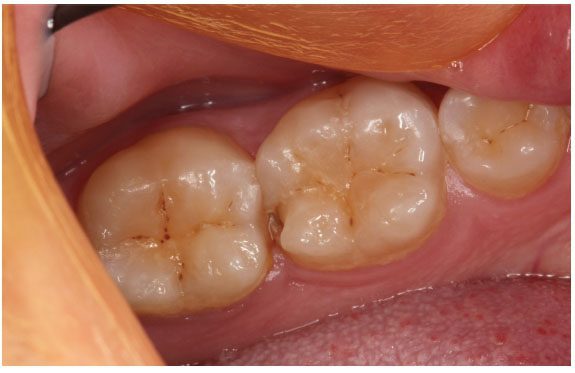

But lift the veil of the anterior teeth and gain access to the posterior teeth. Surprisingly there is a breakdown on the distal aspect of the lower left first molar!.

Let's presume that the bitewing radiograph show no caries on the mesial aspect of the second molar tooth nor on the mesial aspect of the first molar tooth itself. The only breakdown is the lingual aspect of the distal marginal ridge and a small buccal pit.

This tooth needs restoring. What is the restorative material of choice to provide the patient with a long-lasting definitive restoration? Should it be an amalgam, a composite, a ceramic inlay or a cast gold inlay. Does the tooth need a crown? And what about the buccal caries?

In a discussion in a recent study club meeting many in the group expressed the opinion that the tooth be best restored with a composite restoration. Is that what you would have in your mouth?

Would the composite restoration restore the tooth to its original anatomy providing a good contact and marginal ridge?

Although the extent of the caries appears to be limited, the chances are that the tooth destruction is extensive.

Would you not consider a cast gold inlay or ceramic inlay to provide the clinical excellence needed to restore this tooth for long-term health?